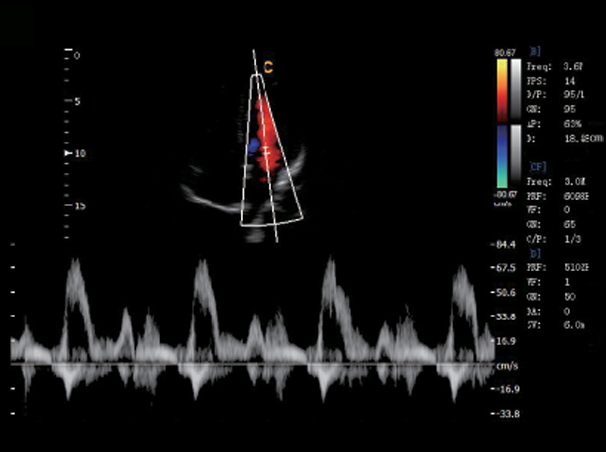

Umbilical Cord,PW Mode

Blood Flow of Mitral Valve, PW Mode